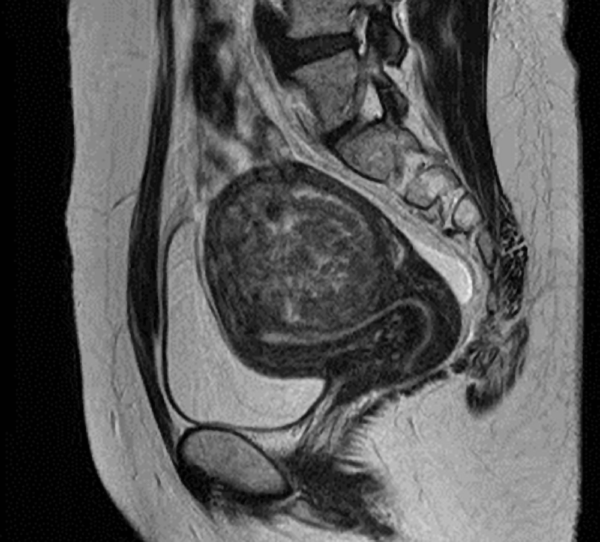

以下のMRI画像は下腹部縦切りの断面で画面右が背中です。

4cmの筋層内筋腫で「子宮鏡は無理」と言われ、開腹手術の予定でしたが、子宮鏡で摘出し妊娠出産できました。

多くの医師は「筋層内筋腫は子宮鏡で取れない」と思っています。